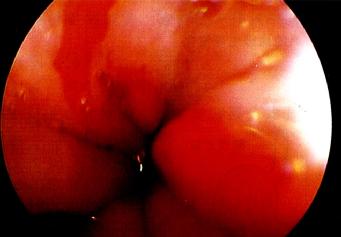

典型的Barrett食管是在胃食管交界上方出現(xiàn)紅色的柱狀上皮區(qū),部分患者可見(jiàn)反流性食管損傷的征象?;顧z可證實(shí)并找到柱狀上皮化生。